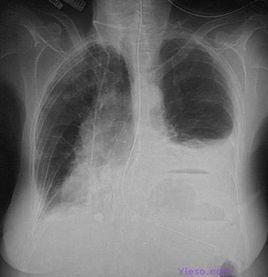

3.X線檢查:少量積液時肋膈角變鈍,中等量積液可見大片緻密陰影,肺底部積液可見患側“膈肌”升高,改變體位胸水可流動。